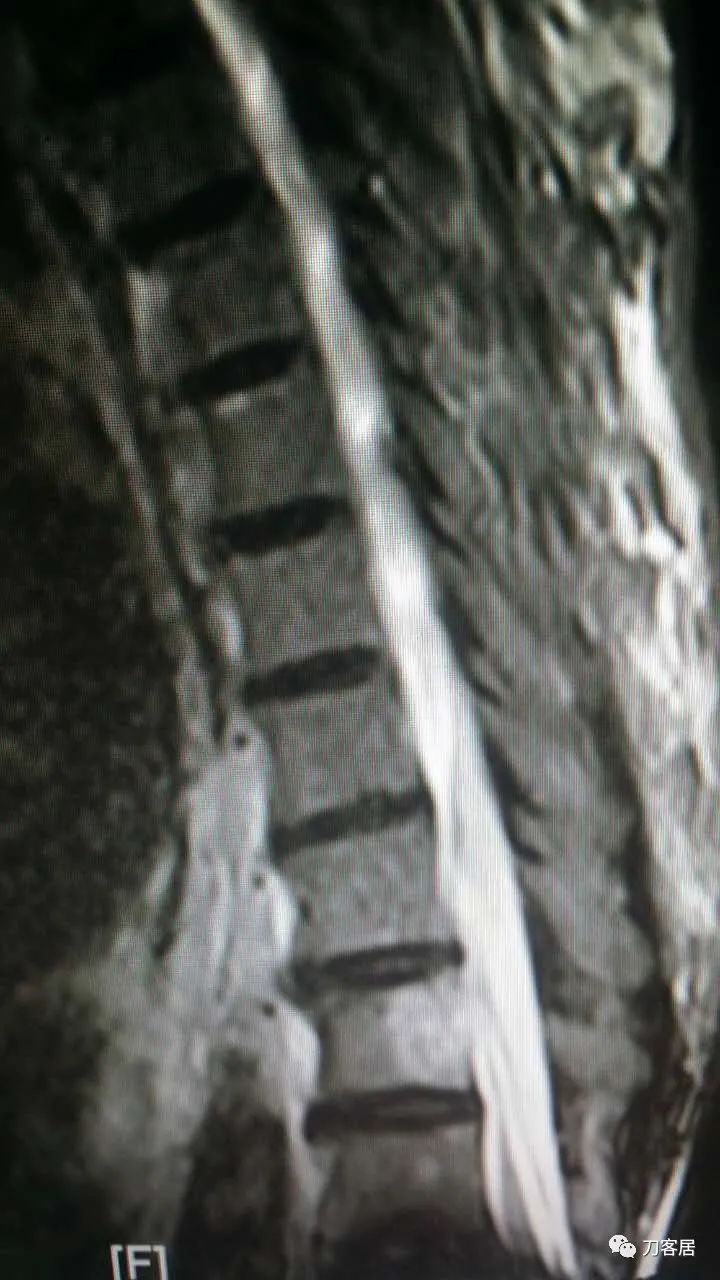

加注图23. 8月20日复查腰椎MRI,血肿占位缩小。

加注图24. 8月20日复查腰椎MRI,血肿占位缩小。

教授,早上好!这是上午刚复查的磁共振,血肿小多了。左腿还是有酸痛,这两天比刚穿刺完明显,但是肌力还是好的。

加注图25. 8月20日腰椎MRI与17日MRI对比。(此图与加注图26是一样的)

加注图26. 8月20日腰椎MRI与17日MRI对比。(此图与加注图25是一样的)

加注图27. 8月20日腰椎MRI与17日MRI对比。上面的日期清晰一些。

加注图28. 8月24日复查的腰椎MRI

不错,这是多少天的?完全消失了。

有,薄薄一层,还没完全消失,比之前又减少了 。